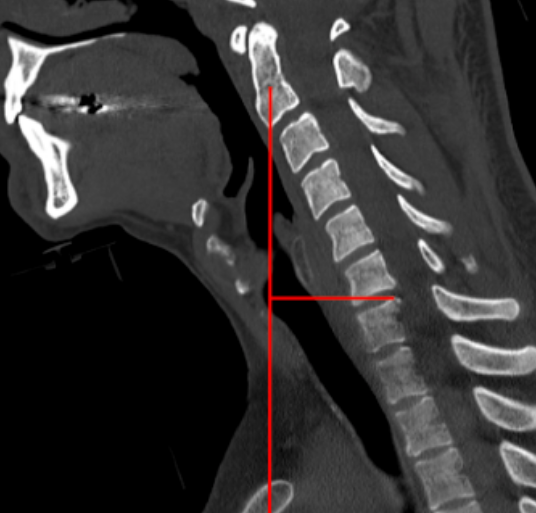

Image Type Cervical Spine X-Ray CT Scan MRI Scan Atlantodental Interval (ADI) Basion–Axial Interval (BAI) Basion–Dens Interval (BDI) Canal Occupying Ratio (COR) Clivo-Axial Angle Facet Joint Overlap (Percent Overlap Method) Facet Joint Step-Off/Dislocation Grabb-Oakes Measurement (pB - C2 line) Occipital Condyle–C1 Interval (CCI) Posterior Atlantodental Interval (PADI) Power’s Ratio Sagittal Vertical Axis (SVA) Segmental Angle Translation on Sagittal Reconstruction